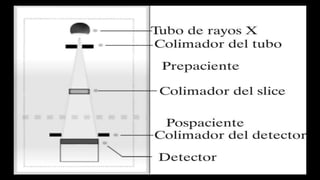

El documento define los conceptos básicos de pixeles, voxels y principios de calidad de imagen en tomografía computarizada. Explica que los pixeles son unidades de información en una imagen y los voxels son unidades de volumen que representan pixeles en secciones de corte. También describe factores como resolución espacial, de contraste y temporal que afectan la calidad de imagen, así como posibles artefactos.